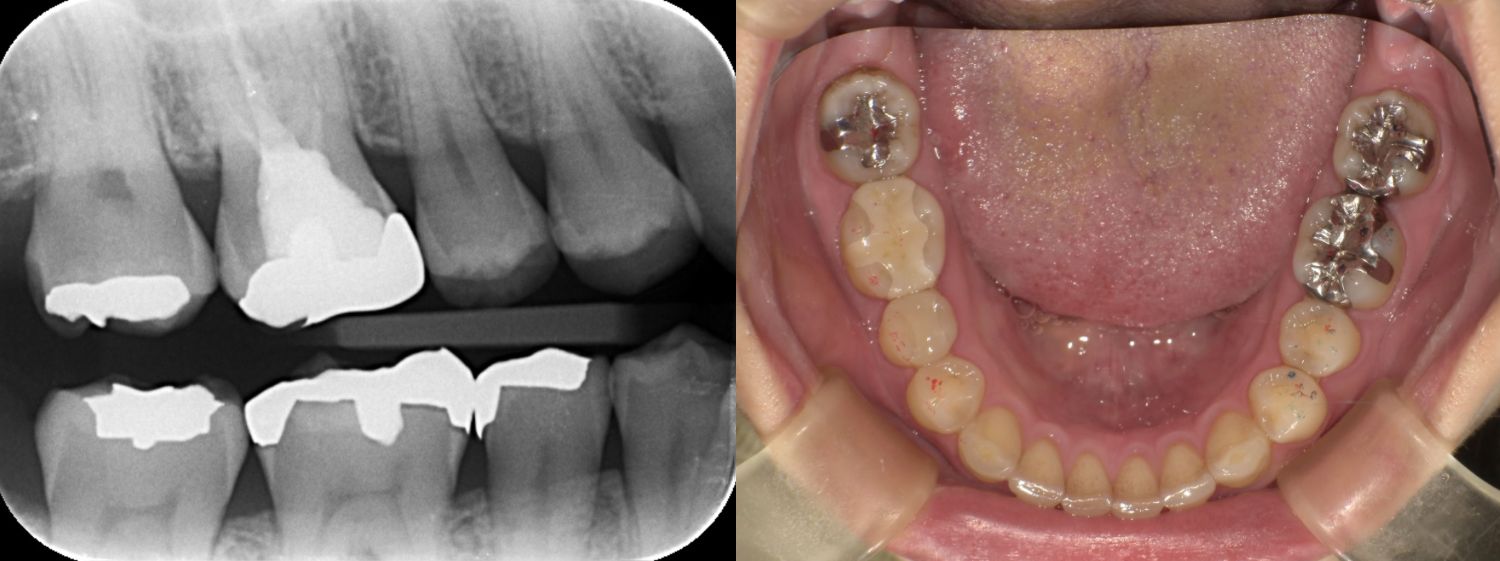

2025/04/22 セレック

SY1443様

通院時年齢 47歳

性別 男性

通院目的 銀歯を白くしたい

診断 銀歯による不適からきたう蝕

処置内容 (または主訴) セレック治療

通院期間 1歯1日(しっかりとした健康な歯肉の状態にまずはしてからの治療になります)

費用

セレック治療 1歯77,000円

リスク・副作用

銀歯直下によるう蝕が広範囲に広がっていた際には神経処置になることがありその場合には1日でセレックに置き換える治療から神経を保存する治療もしくは神経を除く処置に移行する場合があります。 研磨や調整が難しく定期的なメンテナンスが必要になることがある、自由診療となるため費用が高額となる